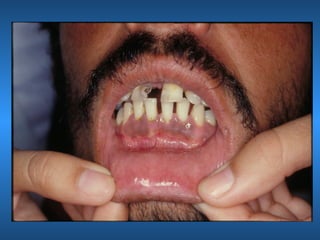

Torus

• Mandibular

• Paltino

• Etiologia